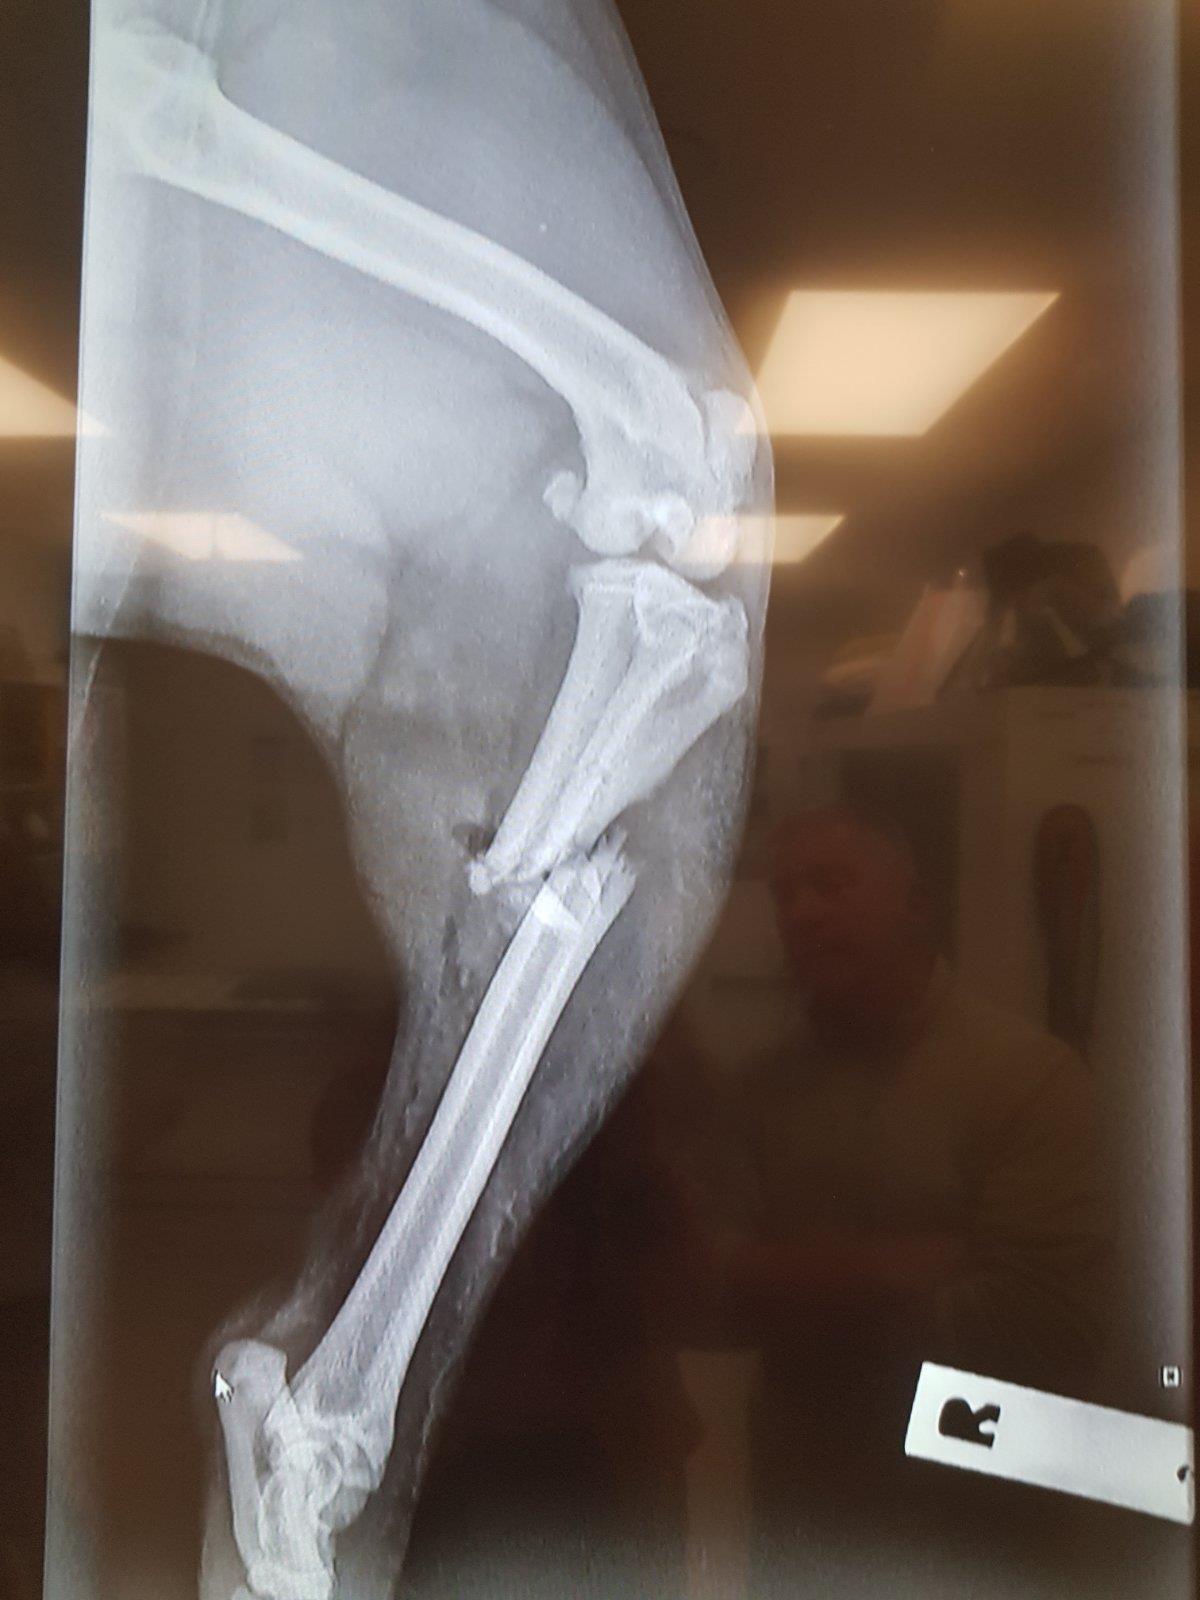

• The break

She definitely did a good job of breaking it!